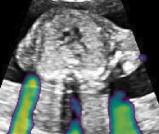

Fig. 9 qualitatively shows that shadow confidence maps are able to improve the performance of US image fusion algorithms with different weighting strategies. Fig. 9 also shows the difference between adding two different types of confidence maps. These two types of confidence maps are generated by the confidence estimation network which are separately trained by either MSE or Sigmoid loss. Fig. 9 (a) to (d) illustrate image fusion results for the same case using different combinations of weighting strategies and loss functions. The difference maps indicate that shadow confidence maps are capable of improving image fusion performance. Fig. 9 (e) to (h) show image fusion results on four different cases. We randomly select two positively affected cases (Fig. 9 (e) and (f)) to show visual improvement. We additionally show two randomly selected examples (Fig. 9 (g) and (h)) that don’t show perceptually significant improvements after adding shadow confidence maps. Quantitative evaluation for image fusion is not possible because of lacking a ground truth for US compounding tasks.

The proposed method generally outperforms the baseline and the proposedAG method, thus we only integrate the shadow confidence maps generated by the proposed method () into the weighting strategy in [39]. In detail, the probability value of each pixel in a shadow confidence map is multiplied to the original weight of the same pixel computed in [39]. The generated new weights are normalized as described in [39] and then are used for image fusion. The data set in this experiment is same as used for [39].